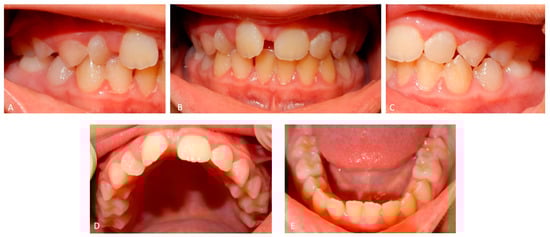

2.3. Father